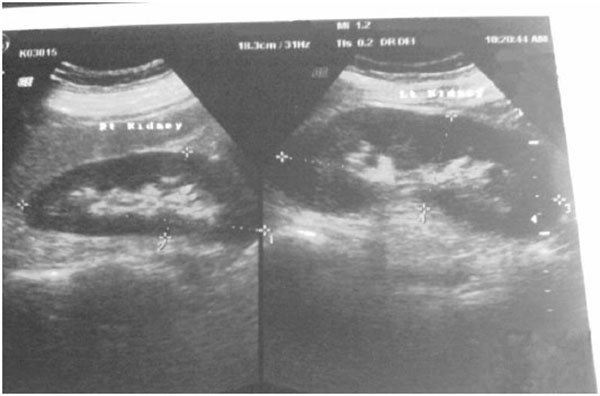

A 32-year-old man who was normotensive and not diabetic was referred from a local hospital with the diagnosis of AKI. His illness started three days prior to admission when he took a locally available energy drink(Moon Power) and felt very hot and restless. He developed severe anorexia, nausea and vomiting three hours later followed by decrease in urine volume for one day. He also developed mild puffiness of the face and feet. He was referred to us on the 3rd day when his serum creatinine was 6.8mg/dl.He denied taking any medication or herbal products recently. On examination, he was looking ill and had mild ankle edema. His pulse was 96/min and BP 160/80 mm Hg. Systemic examination was unremarkable. His bed side urinary albumin was positive (1+) but there were no red blood cells or casts on routine microscopic examination of urine. Renal function test revealed urea 168 mg/dl, serum creatinine 7.2 mg/dl and TCO2 18mmol/L on serum electrolyte test. Urinary total protein revealed 0.75 gm/day and ultra sonogram of kidneys and urinary bladder showed bilateral swollen kidneys (Fig. 4). His serum creatine phosphokinase was 7280 U/L (24-195U/L). All other markers of infection were negative. He was treated with two sessions of dialysis, thereafter his serum creatinine steadily declined without dialysis and finally he was discharged on 10th day with serum creatinine of 1.4 mg/dl.